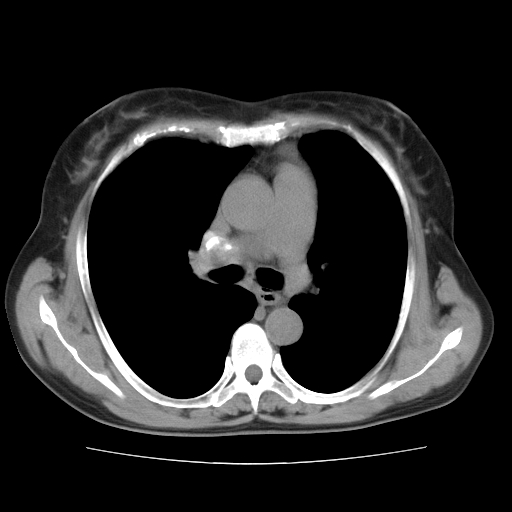

标题: CT10838:女性,56岁,是上腔静脉钙化还是淋巴结钙化?

女性,56岁临床诊断为胃贲门ca,术前检查发现,此钙化灶,对此科内稍有争论!请各位老师看看!是上腔的还是淋巴结的?有意义吗?

淋巴结钙化,上腔静脉在外侧可看到.

支持淋巴结钙化,气管前胸骨后也有.

胸锁关节层面的是淋巴结钙化,气管前腔静脉后的钙化灶占了4个层面,不知层厚是多少?看样子应该是7--10毫米之间,那么这病灶最小纵径得有28毫米!应该提示点什么了,没传肺窗,估计肺内没有病变?

左锁骨下静脉和头臂静脉会合后形成是上腔静脉,此钙化位于两血管回合的腔静脉后方、气管右前方,这个位置没有其他结构,应该是淋巴结钙化。一般多为淋巴结核后钙化,没有临床意义。